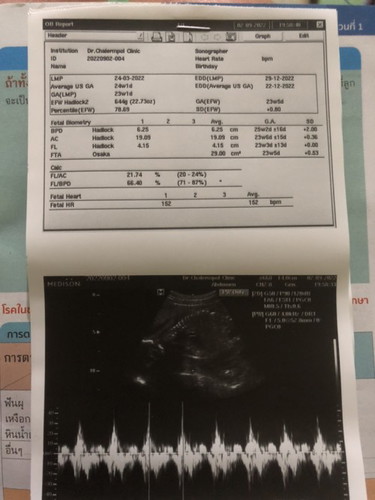

23w2d กำหนดคลอด29ธันวาคม65 น้ำหนักน้องได้644g แม่บ้านอื่นน้ำหนักได้เท่าไหร่แล้วบ้างคะ🥰